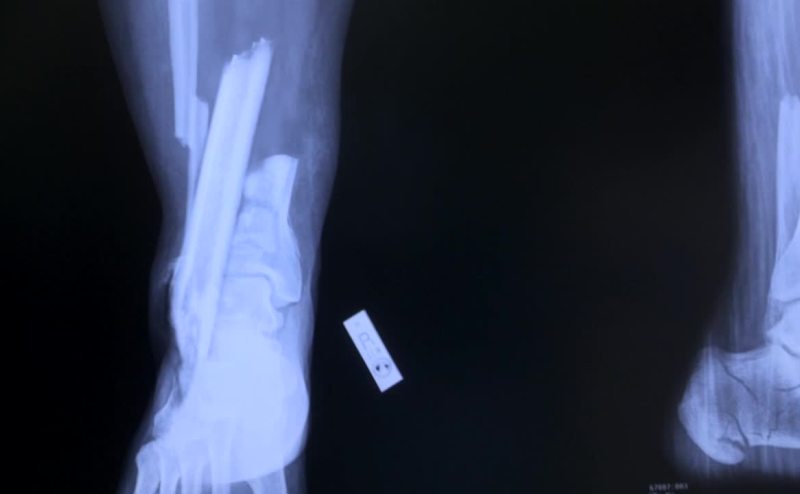

The tibia bones were driven into the bottom of the feet.

The heel bones were fractured bilaterally.

- The impact was vertical. - Vertical?

Yeah, you see it with jumpers all the time.